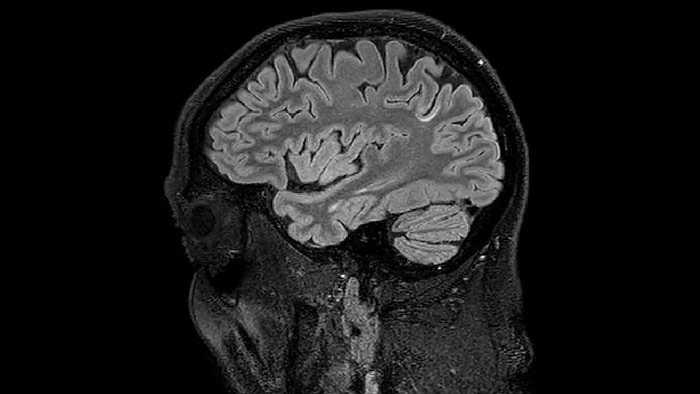

At UBC, a lot of the MS-related work focuses on myelin imaging. “We're born with very little myelin and that increases as the brain grows, which is important for nerve signal propagation. Multiple sclerosis on the other hand, degenerates the myelin with the opposite effect. So, myelin has a really important role in brain function, and having a tool that measures myelin can be extremely useful, we feel,” says Dr. MacKay.

Myelin water imaging (MWI) is a breakthrough technique that was pioneered at UBC for measuring myelin content in the brain, in vivo. “Because the T2 time of water in myelin is much shorter than the T2 of water in the intraand extracellular spaces, we can separate out the myelin water signal.”

The techniques for measuring myelin have changed a lot over the years. “Since we are using the Elition, our myelin water images are much better. We're now acquiring 1 x 2 x 5 mm voxels and displaying at 1 x 1 x 2.5 mm. For a whole brain we can now measure the fraction of water in the myelin component in only about five or six minutes,” Dr. MacKay says.

For Dr. Kolind, the Elition excels in advanced neuroimaging for two main reasons. “It's image quality and access to so many different imaging parameters. We’re involved in several multi-center studies, and we can always easily identify the images that came from our Elition scanner, because they are just so beautiful – even though it seems like we’ve set our parameters similarly to other study participants. And as a physicist, being able to do many things, for instance to push resolution and save time, is really helpful.”